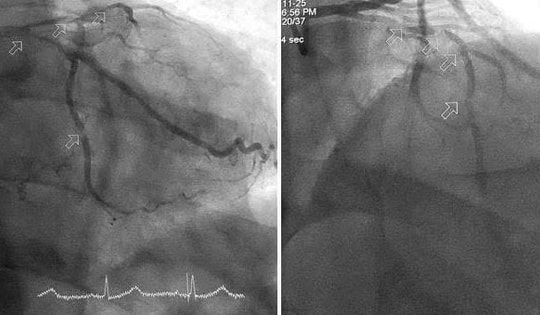

Các bác sĩ Bệnh viện Đa khoa tỉnh Quảng Ninh đã can thiệp cấp cứu thành công cho bệnh nhân 86 tuổi ở phường Quang Hanh bị nhồi máu cơ tim biến chứng sốc tim vô cùng nguy kịch.

Đội cấp cứu tim mạch Giờ Vàng FV cứu cụ ông 80 tuổi thoát đột quỵ và nhồi máu cơ tim cấp

Ông N.V.T. (80 tuổi, Việt kiều Pháp) nhập viện tuyến tỉnh trong tình trạng tức ngực, khó thở, phù phổi cấp, yếu liệt tay chân. Các bác sĩ xác định bệnh nhân có dấu hiệu đột quỵ não và nhồi máu cơ tim cấp cùng lúc - một tình huống y khoa hiếm gặp và nguy hiểm.

Hồi sinh sự sống cho cụ ông 70 tuổi bị nhồi máu cơ tim cấp trong đêm

Mới đây, vào đêm 3/11, đội ngũ y bác sĩ của Bệnh viện Đa khoa khu vực Cẩm Phả (tỉnh Quảng Ninh) đã "hồi sinh sự sống" cho cụ ông Hà Huy H (70 tuổi, trú tại phường Mông Dương) bị nhồi máu cơ tim cấp nguy kịch...